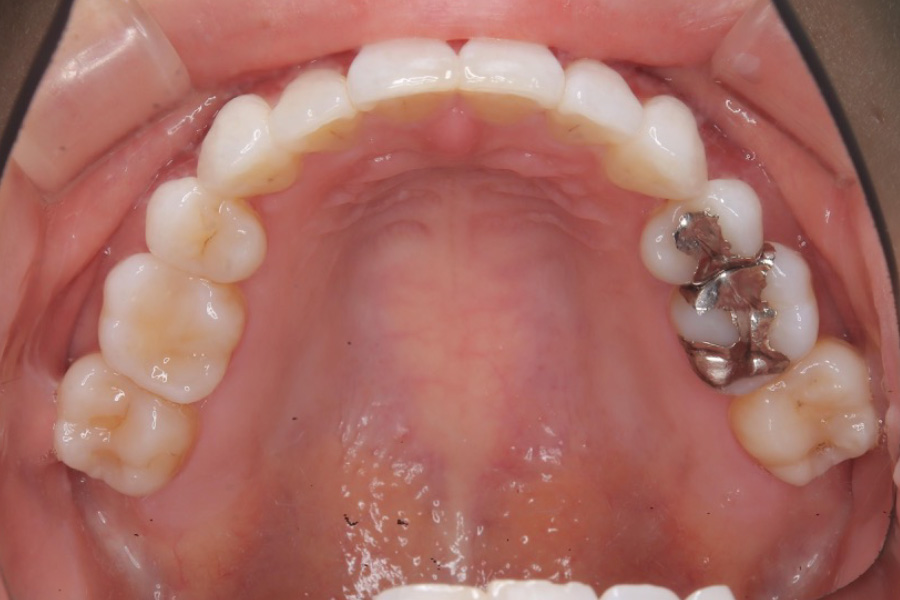

【20代女性】

八重歯、下の歯のガタつきを

インビザライン矯正で治療したケース

治療前

主訴 八重歯、下の歯のガタつきが気になる

治療内容 インビザライン矯正

小臼歯抜歯